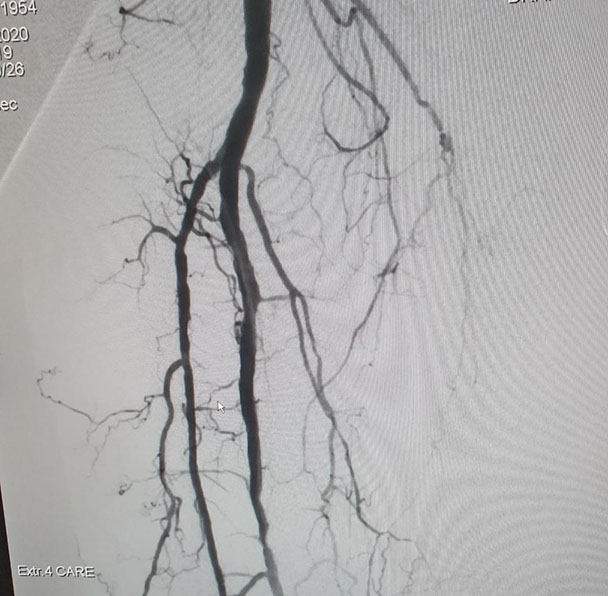

El Dr Sergio Raul Ludueña Jefe del Servicio de Hemodinamia de INCOR nos comentó sobre procedimiento realizado en el día de ayer en en el Servicio. "Queremos compartir con ustedes si bien no es un caso coronario , es un paciente obeso mórbido, diabético, con amputación supracondilea de miembro inferior izquierdo hace 3 años y actualmente con isquemia critica de miembro inferior derecho, con oclusión de ambas tíbiales y sin circulación en el pie".

Se realizó un abordaje híbrido con el Dr. Alejandro Flores, y se re canalizó ambas arterias tíbiales. Procedimiento inédito en nuestra provincia.

Las imágenes siguientes son previas al procedimiento y posterior se ve ambas arterias tíbiales permeables, y circulación en el pie

El procedimiento lo realizo el equipo de Hemodinamia de INCOR dirigido por el Dr. Ludueña junto con la intervención del Dr. Alejandro Flores (Flébologo y cirujano vascular)